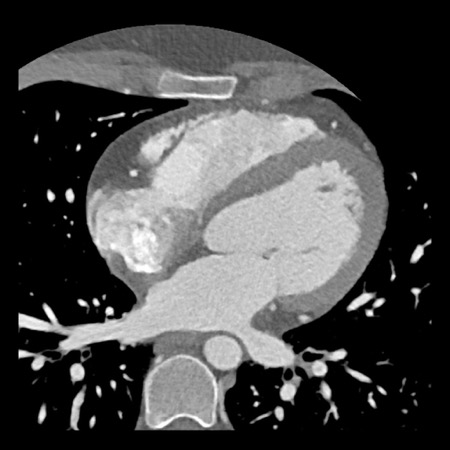

case 4 – CAD-RADS 3/P1/I+ thrombus left ventricle

First, scroll through the CTA images.

How would you describe the findings on the coronary CTA?

The findings are:

- Moderate (50-69%)

stenosis in the proximal LAD caused by a non-calcified plaque. - Variant of

sinoatrial (SA) nodal artery. The artery usually arises from the RCA as a second

branch after the conus artery, however in this case it arises from the LCX,

courses behind the aorta, anastomosing with the right atrium and with a small

branch supplies the SA-node of the heart. - Thrombus in the

apex of the left ventricle. - CTP was performed

in this patient. CTP showed a perfusion defect at stress imaging in the

territory of the LAD (I+), at rest no perfusion defect was visible.

This patient classifies as CAD-RADS 3/P1/I+, which means

this patient requires further investigation.